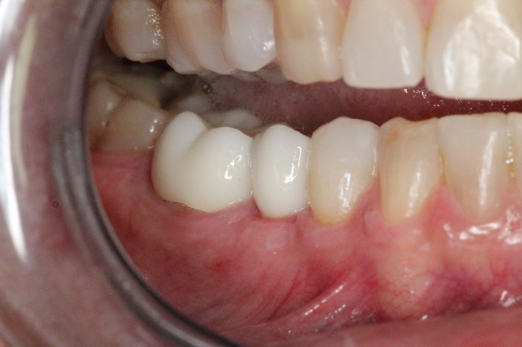

Fig 6. After splint removal (12 weeks postoperatively).

Figure 6

Fig 7. 12 weeks postoperatively.

Figure 7

Figure 3 through Figure 5 show the fitting of a one-piece multiple splint using a light-cured acrylic, along with flowable composite to adhere the splint to the three ceramic dental implants. The splint was to remain out of occlusion, without any occlusal forces for the 12-week osseointegration period. The patient was instructed to chew on the other side of her mouth for the 12 weeks before returning to the dental practice for simple removal of the splint. Removal of the splint revealed optimum results. The soft tissues were pink, with keratinized gingival margins completely surrounding the ceramic implants and consistent with what most dentists observe with the periodontium around periodontally healthy natural teeth (Figure 6 and Figure 7).